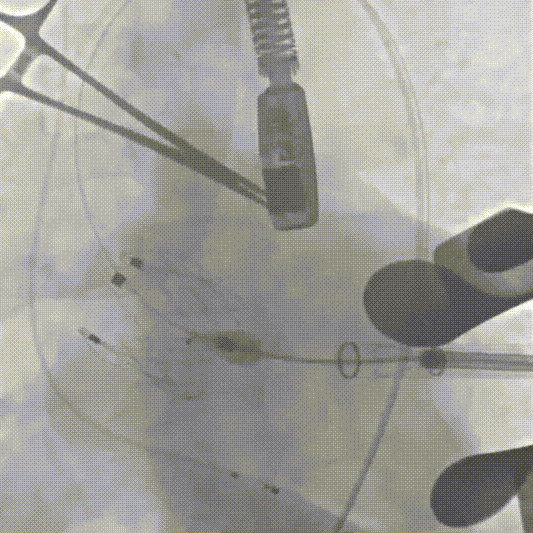

手术过程中,团队严格按照标准操作流程实施。自介入器械导入至瓣膜释放完成,器械用时约10钟。整个过程中,手术团队通过右冠窦居中造影、定位件入窦确认、释放后联合超声与造影评估,确保了瓣膜定位精准、释放平稳。术中超声评估显示无瓣周漏,血流动力学表现良好,手术过程顺利。

定位件跨瓣打开,调整右窦定位件位置,下拉入窦

造影确认定位件入窦底

释放瓣膜

最后一枪造影,基本无瓣周漏